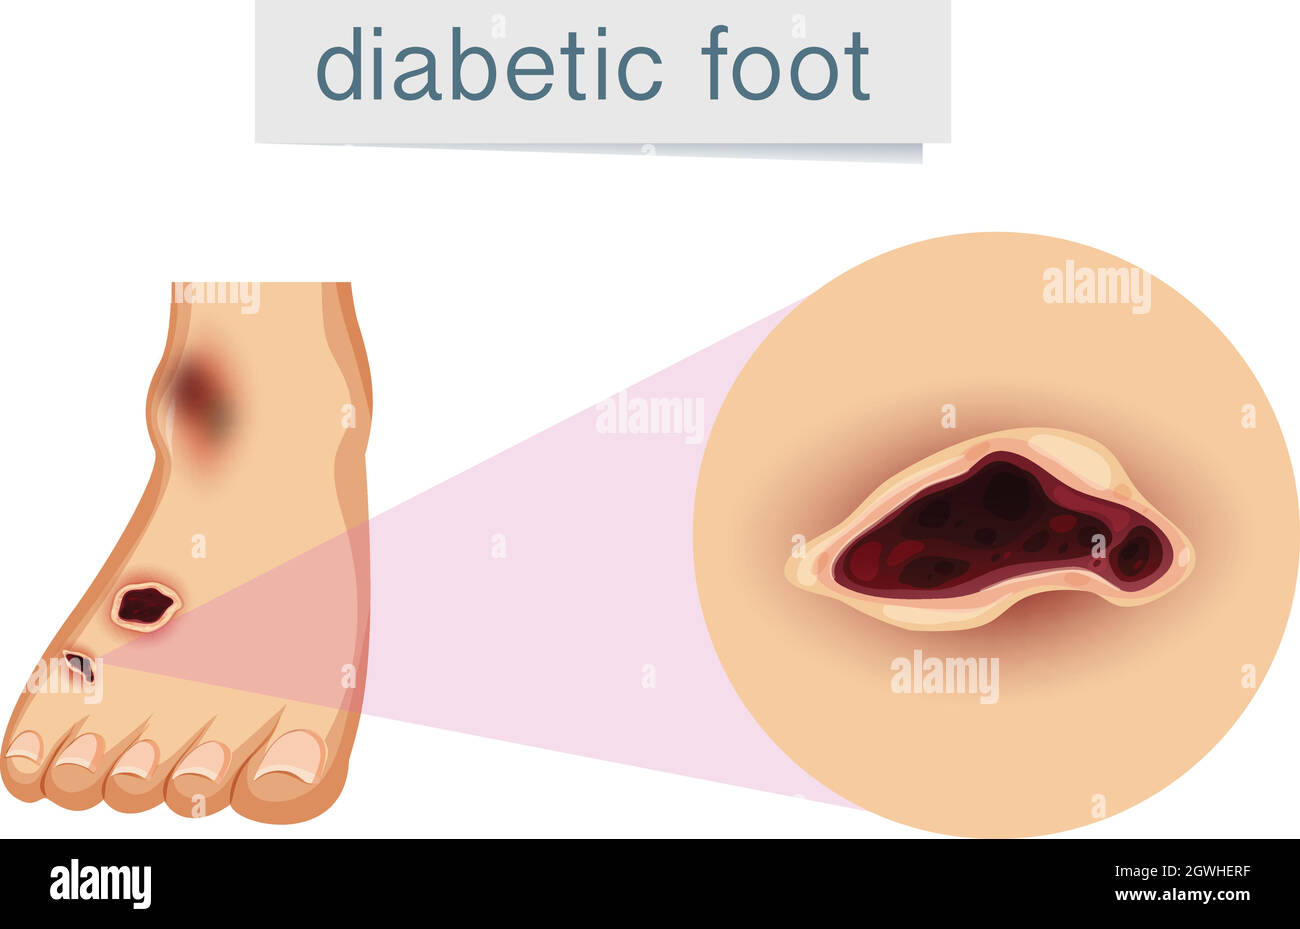

RF2DGMY46–Les verrues du pied sont causées par une infection par un type de virus du papillome humain. Gros plan du HPV

RF2BEFC7R–Douleur au pied et aux jambes. Arthrite et rhumatisme diagramme vectoriel médical orthopédique. Illustration de l'articulation des jambes rhumatismales

RFPKYHHM–La déformation du pied en tant que maladie médicale infographie. Causes de l'oignon. Vector illustration

RFPKYHRK–La déformation du pied en tant que maladie médicale infographie. Causes de l'oignon. Vector illustration